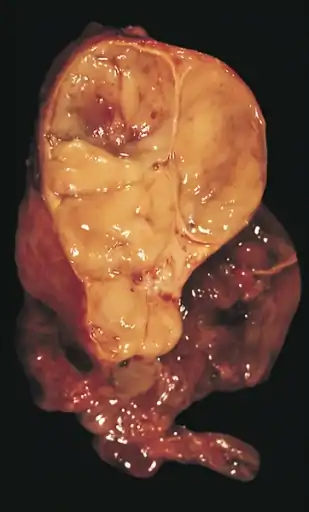

The diagnosis is made via histologic examination by a pathologist, after obtaining a tissue sample of the mass. Final tumor classification and staging is accomplished pathologically after formal surgical removal of the thymic tumor.